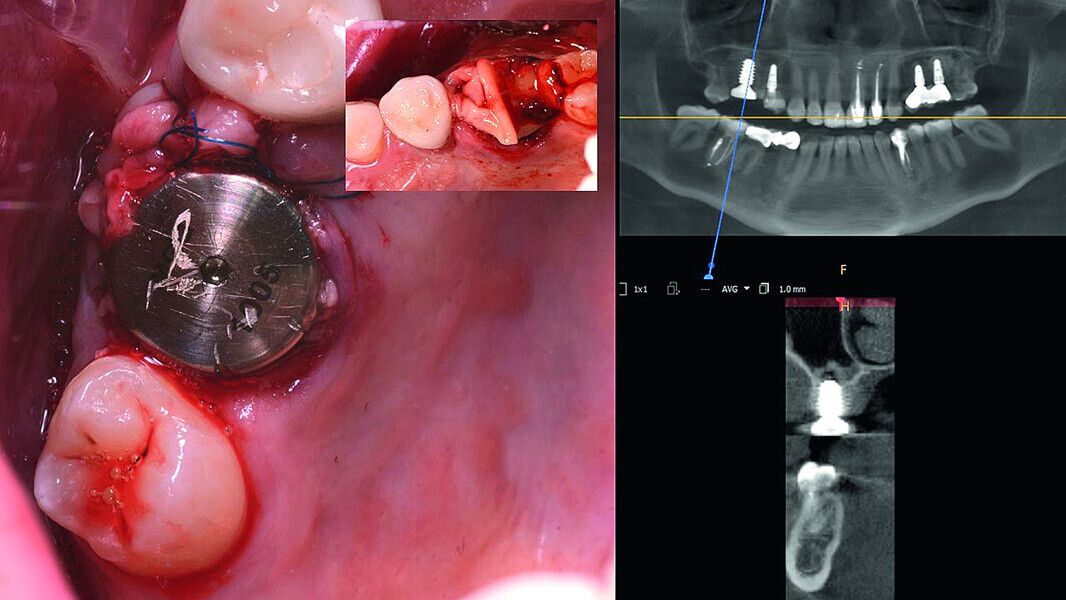

Digital workflow and application of PRF and ozone therapy in oral rehabilitation